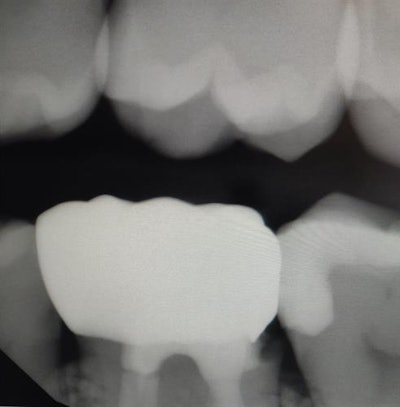

Cummings said there was deep decay lending to deep subgingival margins of the preparation, and multiple unsuccessful attempts were made by the lab to close the margin (the "before" image below, along with an "after" image showing the result of in-office milling).

Before (above) and after (below) images of the crown for Cummings' patient. Images courtesy of Dr. Johnasina Cummings (and released for publication by the patient)."The details that the lab could not capture the first three times, we successfully duplicated and milled on the first try with our new in-office technology solution," she said. "I was able to draw the margin exactly where I wanted it and provide a superior restoration on the first effort.